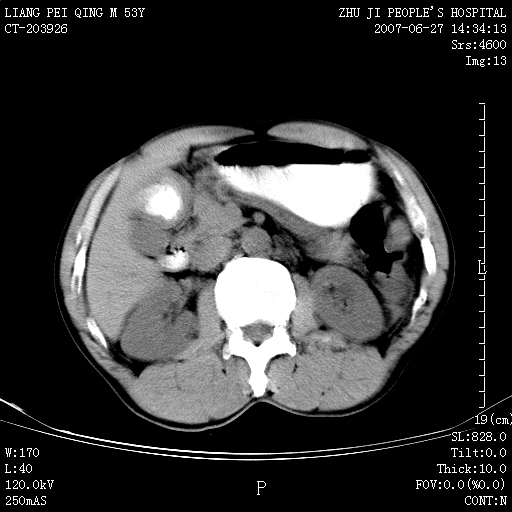

以下是引用余辉在2007-6-27 18:46:00的发言:[br]病灶多发,内可见大片状低密度区,病灶病灶等密度区轻度强化,动脉期后期病灶低密度区与高密度区对度增加,考虑1淋巴瘤2转移瘤3血管内皮细胞瘤(不知有否静脉期及延迟期扫描)

以下是引用zzzzhhhhaaaannnn在2007-6-27 20:44:00的发言:[br]脾脏 肋骨转移可能性大,下腔静脉内有癌栓

以下是引用狙击手在2007-6-28 10:35:00的发言:[br]1:定位:来源于脾脏。2:强化:强化,但不均匀。3:下腔静脉癌栓?下腔静脉充填不均匀与增强时间有关,延时即可明确。4:肋骨破坏?看起来并不确切。综上考虑几个最常见诊断:1;淋巴管瘤;2;血管内皮肉瘤(高度恶性,早期即可转移,常见肝,肺,骨)3;转移瘤(无特征性,只有肝或其它腹腔脏器有类似病变时,才可提示之)